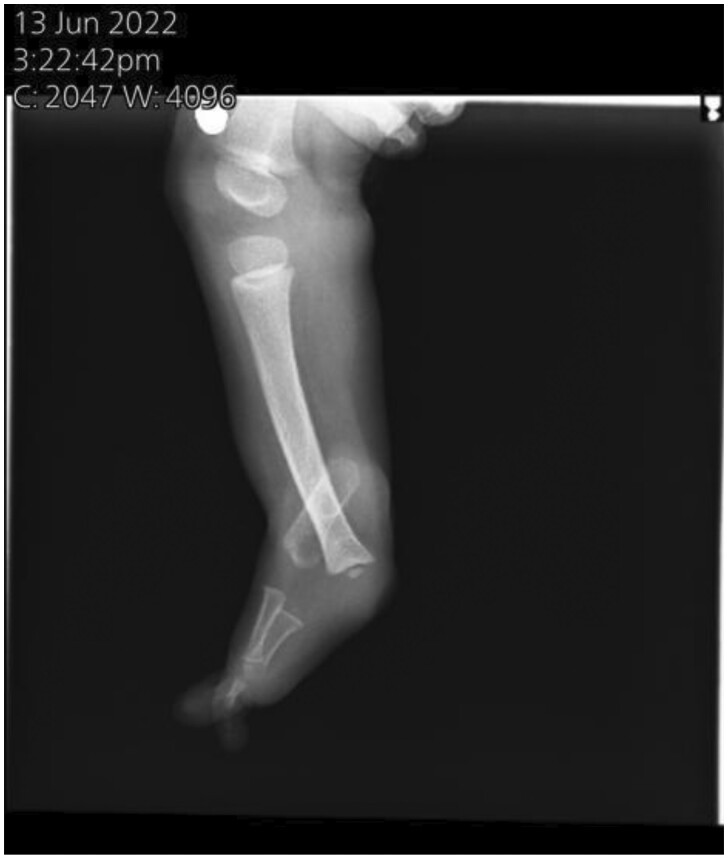

Fibular hemimelia (FH) is a rare congenital abnormality where the fibula is either totally or partially absent. It can occur alone or alongside other skeletal malformations, and in very few cases, it may occur along with non-skeletal anomalies. A 4-year-old female was diagnosed with unilateral right-sided FH, accompanied by limb shortening, a right-side ankle deformity, valgus foot, and 3 lateral rays that had been totally absent since the first week of birth. And she was incidentally diagnosed with spina bifida occulta at a 3-year-old age. FH is most commonly unilateral and mostly affects the right side, leads to a limb-length discrepancy, and maybe comes as a symptom of a syndrome such as Foetus-Fibula-Ulna syndrome and so on. Risk factors include prenatal history, drugs, and no supplementation intake. Together, these elements could be a contributing factor to our condition. The congenital limb abnormalities may be discovered during pregnancy by sonography. If present, other investigations need to be done to differentiate the diagnosis. Treatment according to degree: mild, moderate, and severe cases. In our case, the type 2 FH characteristic was shown by sonography, accompanied by limb shortening, lateral rays absent, and a non-skeletal anomaly (spina bifida). These anomalies very rarely come with each other at the same time. To the best of our knowledge, this case is exceptional in that FH is present at birth alongside spina bifida.